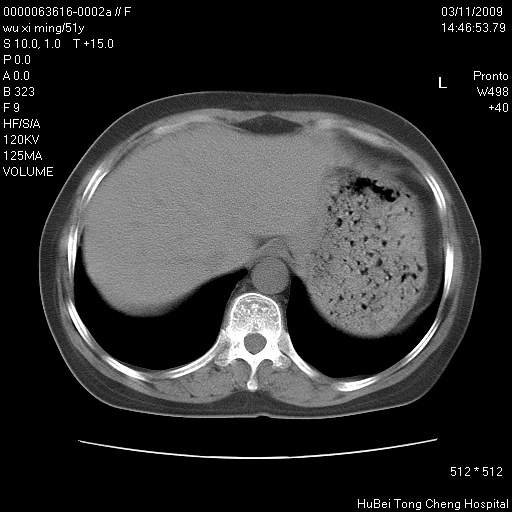

患者 女,51岁。因“胆囊炎,胆囊结石”,行常规术前胸部x线检查发现:右上肺结节病灶,建议行进一步检查。患者无咳嗽、咳痰及咯血等呼吸道症状,近期出现背部疼痛不适。

胸部ct轴位平扫(层厚10mm,螺距1.5,重建间隔10mm;部分层面:层厚3mm,螺距1.0,重建间隔3mm),图像如下:

右肺周围型肺癌伴肺内转移信胸椎转移

右肺周围型肺癌伴肺内转移及胸椎转移。已无手术机会。